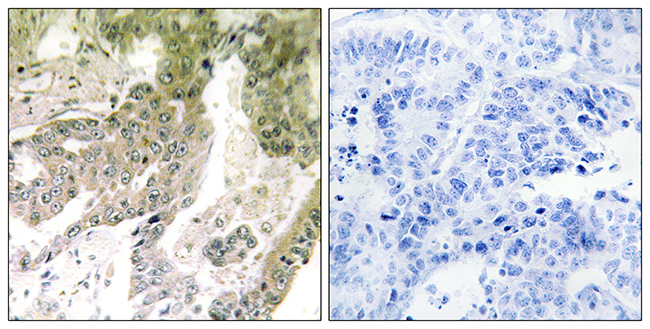

ApplicationsELISA, ImmunoHistoChemistry

ApplicationsELISA, ImmunoHistoChemistry